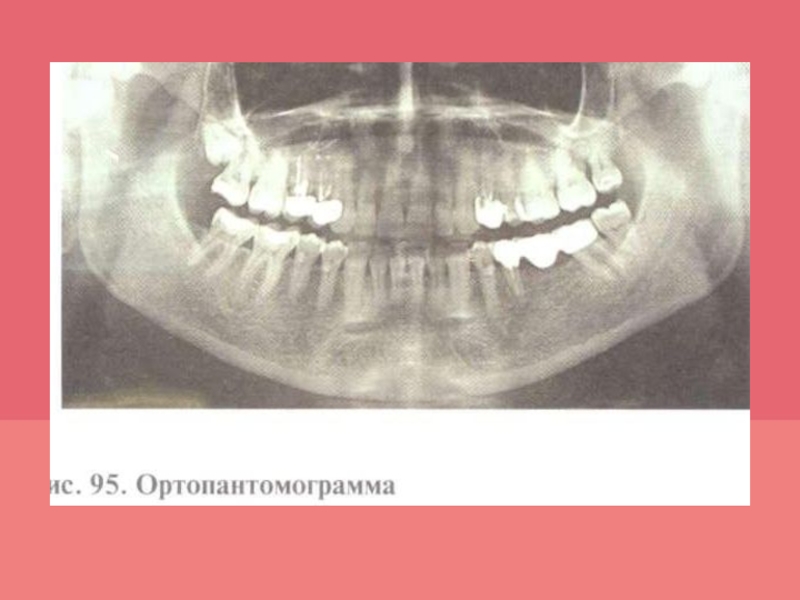

Слайд 32Рентгенологическое исследование

Рентгенологический метод позволяет определить наличие, характер, степень и

распространенность патологических изменений в костной ткани челюстей, провести дифференциальную диагностику

болезней пародонта. Для диагностики изменений пародонта оценивают внутриротовые контактные и интерпроксимальные рентгенограммы; внеротовые — панорамные рентгенограммы и ортопантомограмму, а также проводят трехмерное томографическое исследование.